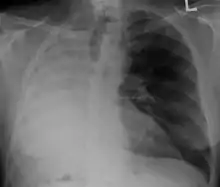

Anatomical Changes

After a pneumonectomy is performed changes in the thoracic cavity occur to compensate for the altered anatomy. The remaining lung hyperinflates as well as shifting over along with the heart towards the now empty space. This space is full of air initially after surgery, but then it is absorbed and fluid eventually takes its place.[9]